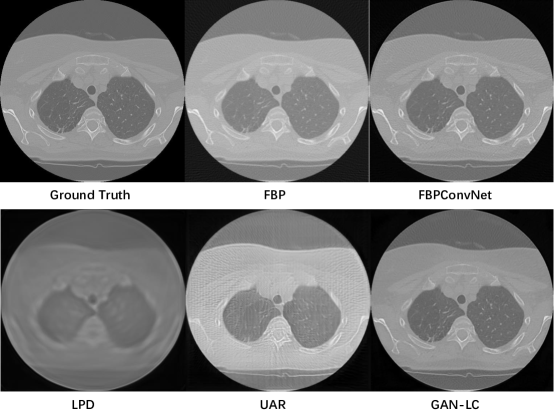

To illustrate the reconstruction performances more clearly, we also show the reconstruction results for testing images in Figure 3. We can see that our network can reconstruct the CT image with higher quality. Due to the space limit, the experimental results of different views and more visualized results are placed in our supplementary material.